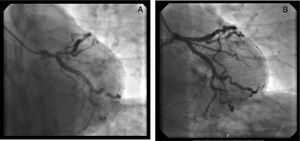

Coronary angiography revealed significant disease in the anterior descending artery - 85% ostial stenosis and 70% proximal stenosis up to the emergence of the first diagonal. No significant lesions were observed in the remaining vessels via angiography. Pre-dilatation with a balloon was performed on the proximal and ostial lesion of the anterior descending artery, and a 3.5×28mm antiproliferative stent was then implanted, with good final angiographic results (Figure 3).